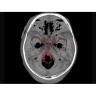

Позволяет проводить комплексные исследования всех анатомических зон, включая нейровизуализацию, ангиографию, исследования органов грудной и брюшной полости. Особенно эффективен для раннего выявления онкологических заболеваний.

Компьютерный томограф GE Brivo CT385 представляет собой современное диагностическое оборудование, сочетающее высокую точность исследований с повышенным комфортом для пациентов. Этот аппарат открывает новые возможности для детальной визуализации анатомических структур.